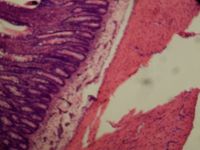

나트륨 흡수는 두 단계로 이루어진다. 첫 번째 단계는 장 상피 세포(장세포)를 통한다. 나트륨은 공동 수송을 통해 SGLT1 단백질을 통해 포도당과 함께 이 세포 안으로 들어간다. 장 상피 세포에서 나트륨은 나트륨-칼륨 펌프를 통해 능동 수송에 의해 기저외측 막을 통해 세포외 공간으로 펌핑된다.[40]

SGLT1 단백질을 통한 포도당의 상피 세포로의 공동 수송에는 나트륨이 필요하다. 두 개의 나트륨 이온과 한 분자의 포도당 (또는 갈락토스)이 SGLT1 단백질을 통해 세포막을 가로질러 함께 수송된다. 포도당이 없으면 장 나트륨은 흡수되지 않는다. 이것이 경구 수액 염에 나트륨과 포도당이 모두 포함된 이유이다. 수송의 각 주기마다 수백 개의 물 분자가 삼투압 평형을 유지하기 위해 상피 세포로 이동한다. 그 결과 나트륨과 물의 흡수는 설사가 계속되는 동안에도 재수화를 달성할 수 있다.[40]